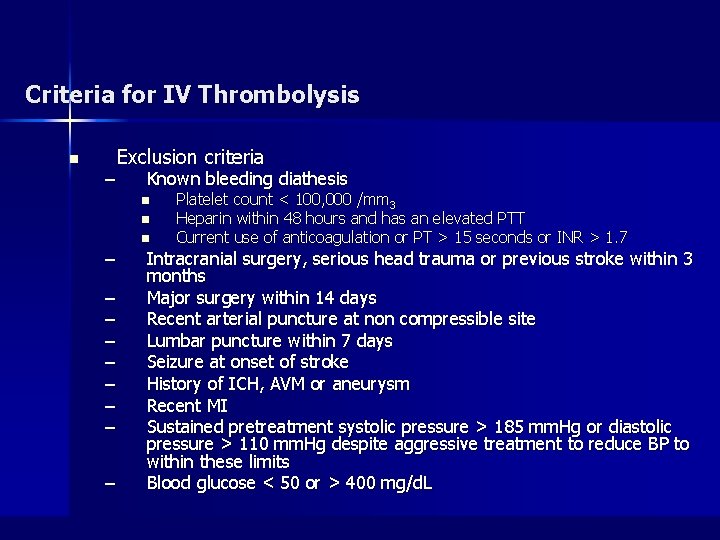

Criteria for IV Thrombolysis n – Exclusion criteria Known bleeding diathesis n n – – – – – n Platelet count < 100, 000 /mm 3 Heparin within 48 hours and has an elevated PTT Current use of anticoagulation or PT > 15 seconds or INR > 1. 7 Intracranial surgery, serious head trauma or previous stroke within 3 months Major surgery within 14 days Recent arterial puncture at non compressible site Lumbar puncture within 7 days Seizure at onset of stroke History of ICH, AVM or aneurysm Recent MI Sustained pretreatment systolic pressure > 185 mm. Hg or diastolic pressure > 110 mm. Hg despite aggressive treatment to reduce BP to within these limits Blood glucose < 50 or > 400 mg/d. L